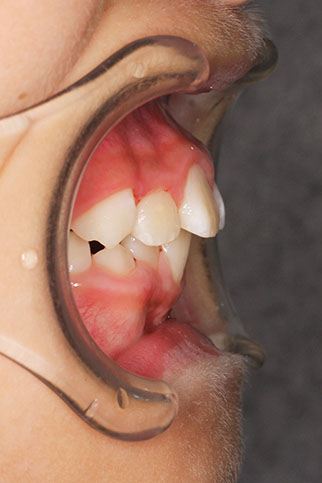

側方歯(犬歯、小臼歯)の生え変わりの時期。 前歯のがたつきを気にされ、小児矯正からの治療を希望されました。 お母様は、矯正治療経験済みですので、治療には前向きで早期治療の必要性を納得されていました。 小児矯正では、永久歯の生え変わるためのスペースを増加させ、がたつきを軽減させることを目的で行います。 残ったがたつきは、全ての永久歯が生え変わってから、本格矯正(マルチブラケット装置での治療)で改善しています。 比較的、叢生量は少ないため、本格矯正は非抜歯にて配列しました。

マルチブラケット 動的治療期間 2年6か月 調整回数16回 特に問題もなく、保定後も安定しています。